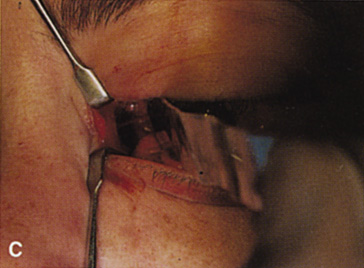

Fig. 11. A. Lateral canthotomy incision is made with straight iris scissors. B. Periosteum is elevated off of the lateral orbital rim. C. Wide undermining allows retraction of the skin incision to permit superior

and inferior osteotomies to be made with the air-driven saw. D. The bony rim has been outfractured. Because of the distensibility of the

skin, it is possible to remove a large bone flap through the small

canthotomy incision. E. The intraconal mass is extracted with the aid of the cryoprobe. F. The bone fragment is positioned for resuturing.

Fig. 11. A. Lateral canthotomy incision is made with straight iris scissors. B. Periosteum is elevated off of the lateral orbital rim. C. Wide undermining allows retraction of the skin incision to permit superior

and inferior osteotomies to be made with the air-driven saw. D. The bony rim has been outfractured. Because of the distensibility of the

skin, it is possible to remove a large bone flap through the small

canthotomy incision. E. The intraconal mass is extracted with the aid of the cryoprobe. F. The bone fragment is positioned for resuturing.

|